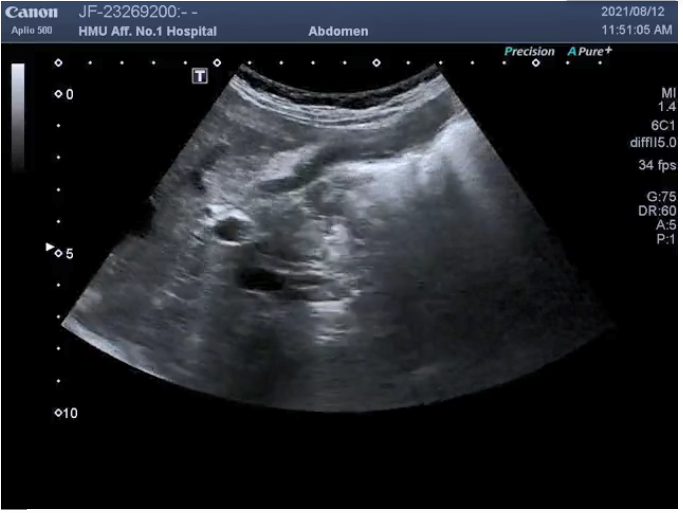

病例六(混合回声型),十二指肠旁强低回声相间混合回声型憩室(此病例由山东中医药大学第二附属医院胃肠充盈超声精品培训班优秀学员、哈尔滨医科大学附属第一医院贾凡医生提供):